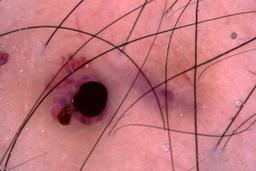

{

"age_approx": 55,

"anatom_site_general": "posterior torso",

"concomitant_biopsy": true,

"dermoscopic_type": "contact non-polarized",

"diagnosis_1": "Malignant",

"diagnosis_2": "Malignant melanocytic proliferations (Melanoma)",

"diagnosis_3": "Melanoma, NOS",

"diagnosis_confirm_type": "histopathology",

"image_type": "dermoscopic",

"lesion_id": "IL_6864076",

"melanocytic": true,

"patient_id": "IP_4659192",

"sex": "female"